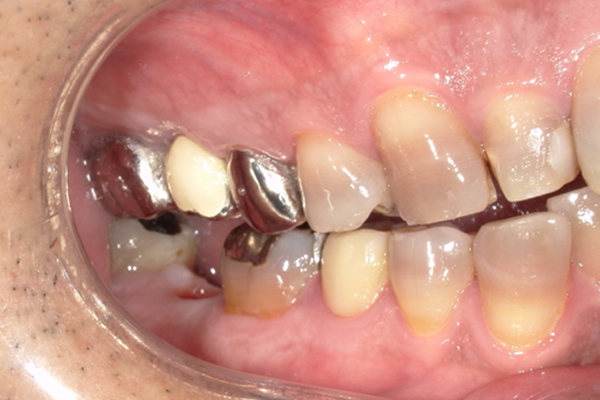

| 主訴 | 歯が痛い |

|---|---|

| 治療内容 | 右上奥歯に対するインプラント治療 (今後右下に対してもインプラント治療を予定) |

| 治療期間 | 6ヶ月 |

| 治療費 | 44万5千円 |

| 治療 リスク | インプラントを埋入したあと3ヶ月程度待ち時間が必要。 その期間は仮歯を使用していただきます。 |